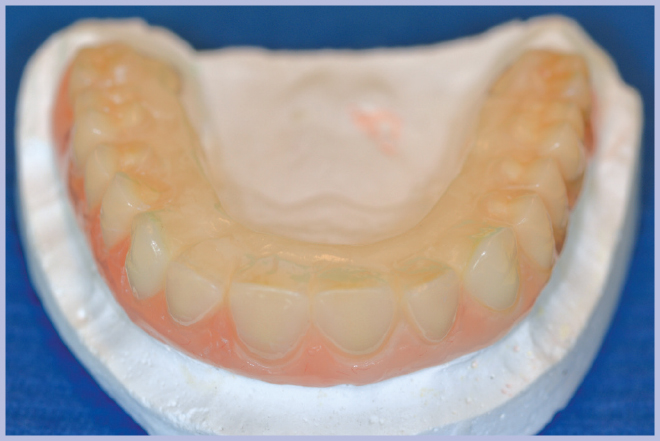

La nuova protesi, realizzata in materiale composito sul modello di quella pre-esistente (Fig. 9), è stata poi ribasata in bocca sull’armatura di rinforzo fissata ai monconi (Fig. 10). Ad indurimento avvenuto della resina per ribasature, si sono rimosse le viti e si è rifinita la protesi. L’operazione di rifinitura da parte del tecnico è di grande importanza, perché si deve il più possibile ridurre l’estensione della flangia vestibolare al fine di favorire una buona detersione da parte del paziente.

- Fig. 9 – Protesi nuova in composito

- Fig. 10 – Fissaggio della protesi sulla struttura metallica